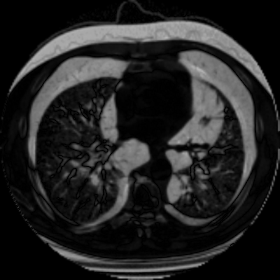

We then test our method on slices of chest CT images obtained from the Open Access Biomedical Image Search Engine [2]. Fig. 10(a) and 10(b) show the source image and target image respectively, and the intensity difference is shown in Fig. 10(c). The registration result obtained by our proposed method is shown in Fig. 10(d) (see also the result with the deformed underlying grid in Fig. 10(e)). From the final intensity difference plot in Fig. 10(f), it is easily to see that our method matches not only the two large components but also the small dot at the center very well. On the contrary, DDemons [47] produces a suboptimal registration result with a significantly larger mismatch of the small component at the center (see Fig. 10(g) and Fig. 10(h)).